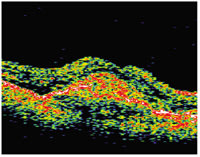

| This patient with

predominantly classic choroidal neovascularization of approximately 6 Macular Photocoagulation Study disc areas (images to the far left) had distance vision of 20/64, near vision of 20/100 and a reading speed of 109 words per minute. At 1 year after an MTS360 procedure (images to the right), distance vision was 20/40, near vision was 20/20 and reading speed was 150 words per minute. At 2 years post-op, distance vision was 20/40, near vision was 20/25 and reading was 171 words per minute. |